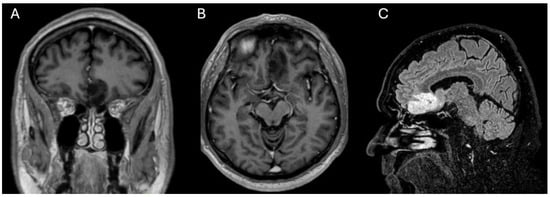

2.1. History and Clinical Findings